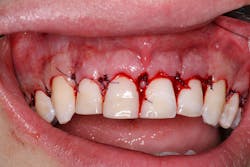

The periodontist would perform the procedure by anesthetizing the patient to perform bone sounding to determine the distance from the most coronal position of alveolar bone to the cementoenamel junction (CEJ) of the patient’s original tooth position.

Typically, after bone sounding, the periodontist will mark on the gingiva with indelible ink, reflect a full thickness flap and perform the osseous surgery. Biological width is maintained by reflecting a full-thickness tissue flap and electing to reduce the bone in an apical direction (3–4 mm apical to the newly selected most apical portion of the crown) to show the desired amount of tooth after the tissue is excised, while maintaining a minimum of 2 mm of keratinized tissue around the new gingival margin. The flap is then approximated at the new and ideal position on the teeth and sutured closed for healing purposes. Approximately 0.5 mm apical gingival creep is anticipated, as it will ultimately follow the height and contour of the underlying bone.